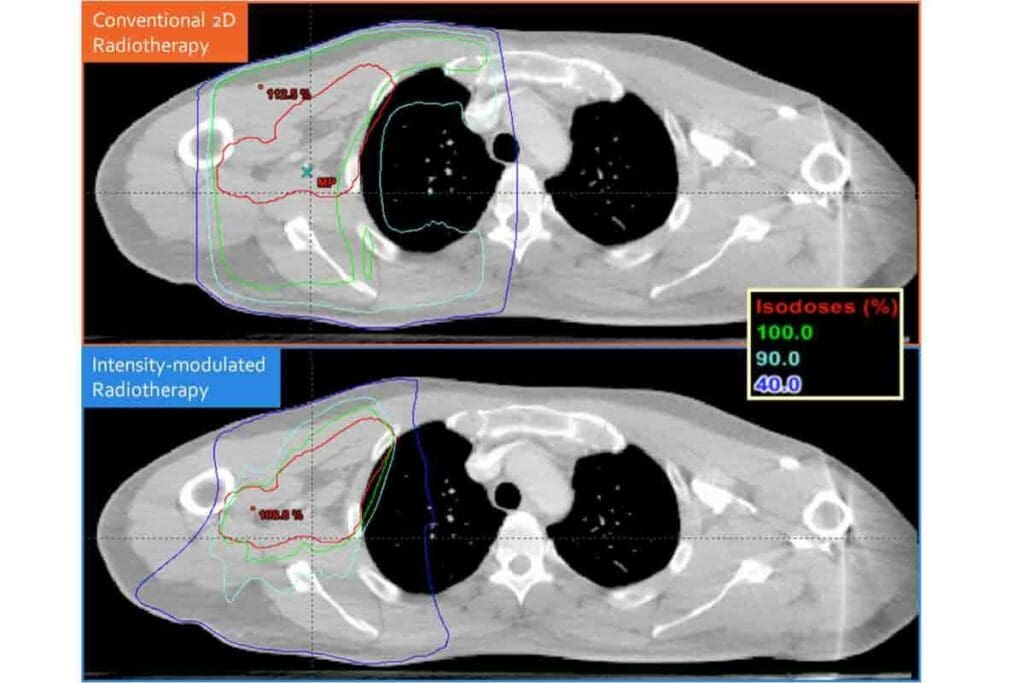

CBCT Radiation Dose Comparison: Medical CT vs. Cone Beam CT

CBCT radiation doses are much lower than those of traditional medical CT scans. This is important for dental professionals and patients to know.

Quantifying the Difference

Research shows CBCT gives a significantly lower radiation dose than medical CT scans. On average, CBCT is about 28% lower in radiation.

Effective Dose Ranges

CBCT scans usually have an effective dose of 80 to 150 microsieverts (µSv) per scan. Medical CT scans, by contrast, often go over 500 µSv or more per scan.

Mean Effective Dose Analysis

Looking at mean effective doses, we see a big difference. CBCT has a mean effective dose of about 1.8 millisieverts (mSv). Medical CT scans have a mean effective dose of around 2.5 mSv.

| Imaging Technology | Effective Dose Range | Mean Effective Dose |

| CBCT | 80-150 µSv | 1.8 mSv |

| Medical CT | 500+ µSv | 2.5 mSv |

This comparison shows the advantages of CBCT in reducing radiation exposure for dental imaging. Choosing CBCT over medical CT can lower patient risk while keeping diagnostic quality high.